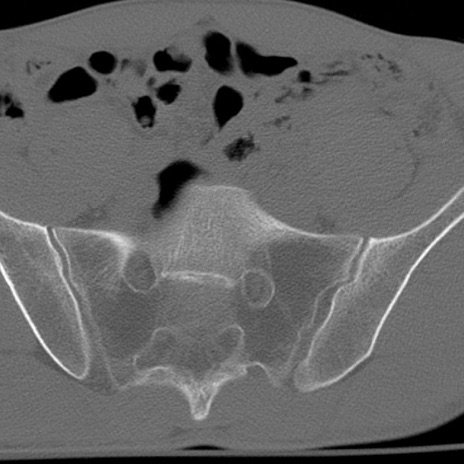

症例3 腰椎CT(横断像)

腰椎CT